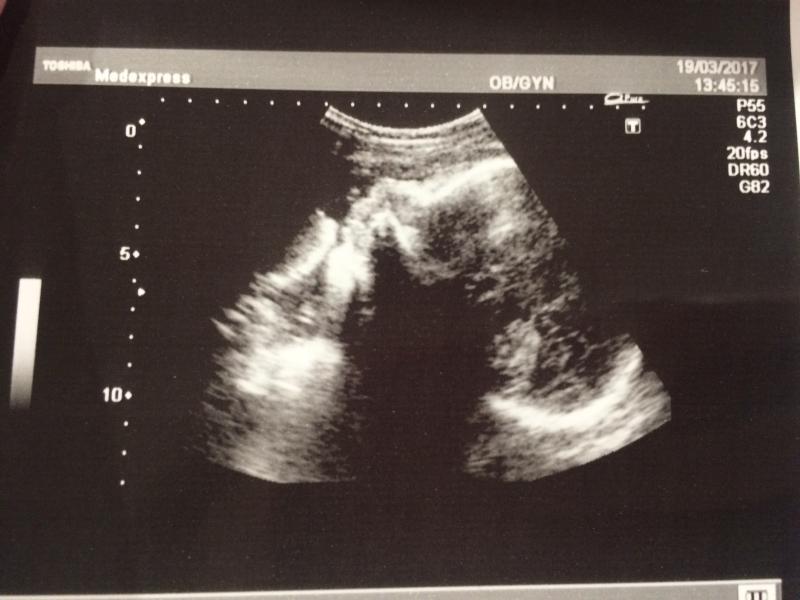

Сегодня сходили на УЗИ к Артуру .

Ни один диагноз поставленный Казьменко не подтвердился.Кровоток не нарушен ,плацента 2 степени зрелости,шейка 29мм зев сомкнут .Всё хорошо ☺

Папа смотрел на нашего мальчика ,ожидал что то другое ,но он уже большой и весь на экран не помещается )))))